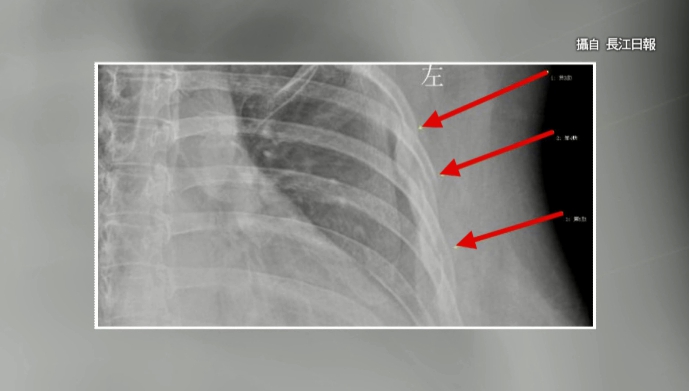

X光照片上標示出3根骨折的肋骨,根據醫師檢查後發現,這名30歲的上班族骨頭年齡竟然高達60歲,而這一切可能都是咖啡造成。

▼一名上班族一天最多可以喝10杯咖啡,小小的感冒咳嗽卻引發3根肋骨骨折(圖/翻攝自長江日報)